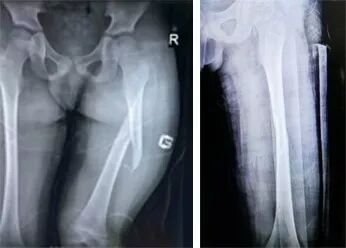

股骨中上段骨折

患者趙某,男,8歲,滑冰時跌倒導(dǎo)致左股骨中上段骨折,患者年齡較小,家屬希望予以保守治療。來到我院富陽骨傷就診后,進行手法整復(fù)、杉樹皮外固定,當(dāng)即復(fù)位成功,一個半月骨折愈合,功能恢復(fù)正常。

手法整復(fù)前后對比圖